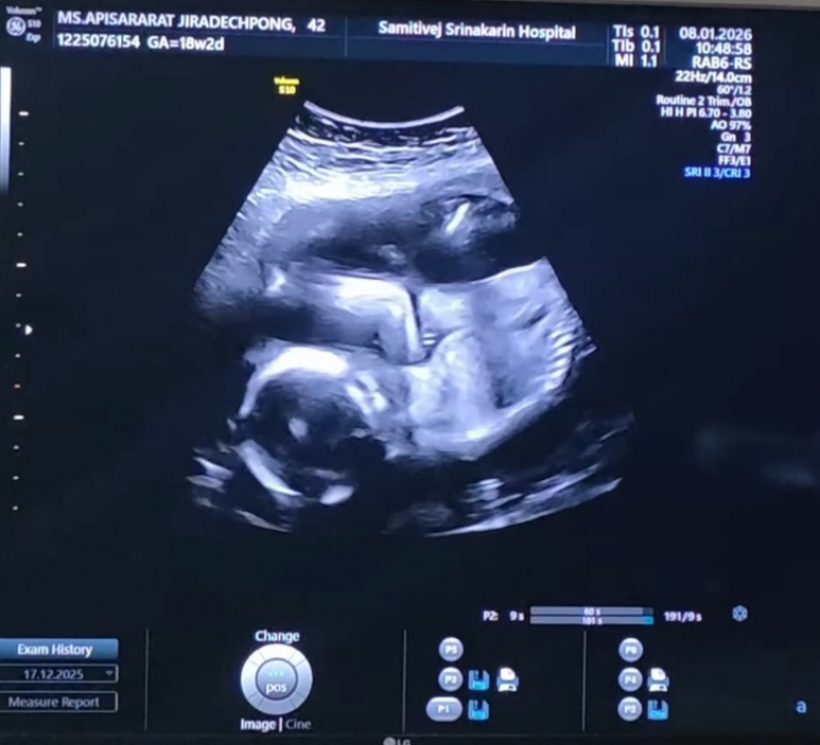

ล่าสุด ลีซอ โพสต์อินสตราแกรม @leesawls14 เผยโมเมนต์อัลตร้าซาวด์ลูกน้อยในครรภ์ภรรยา พร้อมแคปชั่นระบุว่า "รอวันพบกันนะลูกนะ #18w2d #LFbaby"